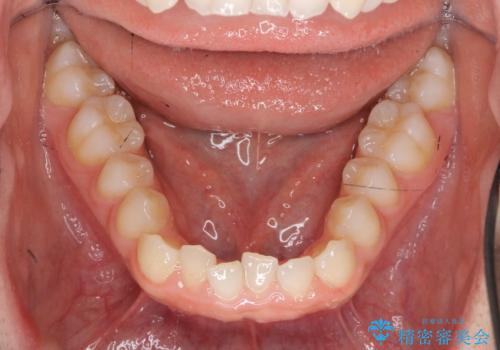

前歯のガタつき・ねじれを治すマウスピース矯正

- 前歯のねじれ、ガタつきを改善し綺麗な歯並びにしたいと希望され来院されました。

マウスピース矯正インビザラインによる矯正治療を計画しますが、マウスピース矯正で治りにくい歯のねじれを事前にワイヤー矯正でしっかりとなおしておくことで矯正治療期間の短縮できるような治療計画を立てます。

マウスピース矯正を始める前にワイヤー部分矯正を行ったことで改善のしにくい歯のねじれをしっかりと治すことができました。